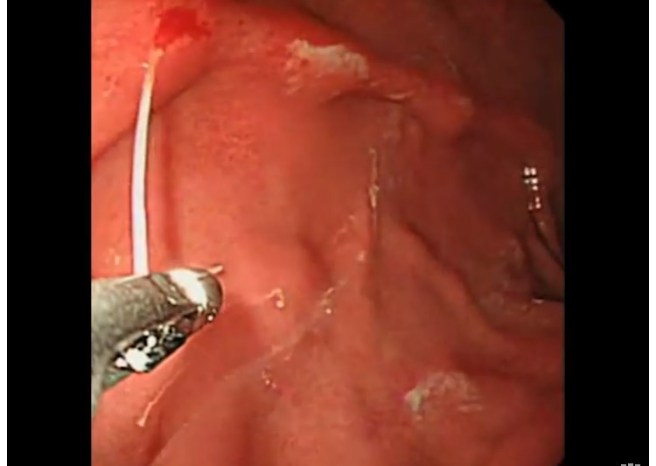

NEJM: Remoção endoscópica de larva parasitária.

Remoção endoscópica de larva parasita em usuário de salmão cru. Dica da página do face do meu “parça” Dr. Arnaldo Gouveia.